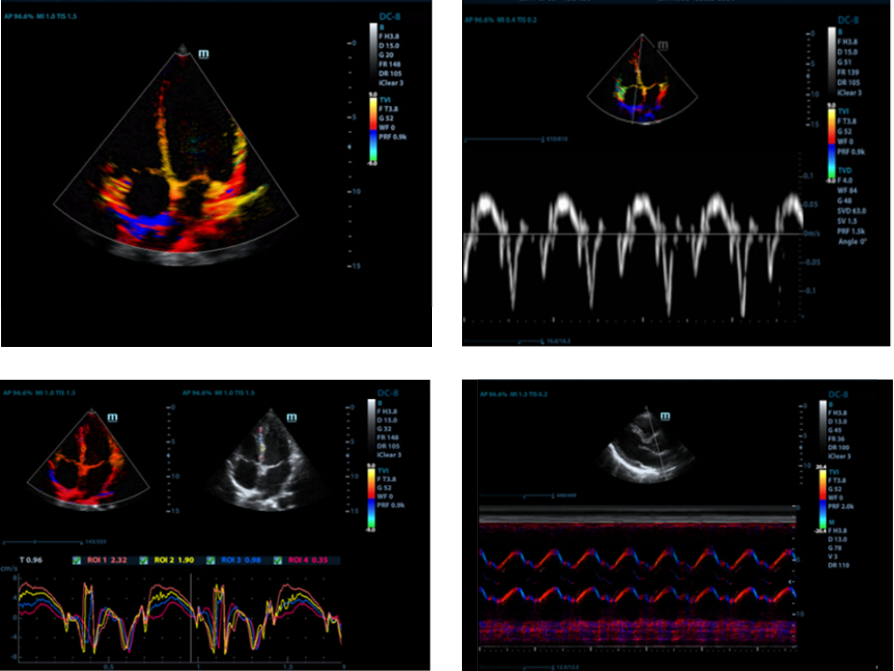

TDI (Doppler tkankowy)

Obrazowanie Tkanek z u?yciem Dopplera - Tissue Doppler Imaging pozwala na ilo?ciow? ocen? miejscowego ruchu i funkcji mi??nia sercowego. Aparat M9 zapewnia kompletny tryb Dopplera tkankowego w celu uzyskania szybszej i bezpo?redniej diagnozy.

Auto EF (automatyczne wyliczanie frakcji wyrzutowej)

Jeden z inteligentnych sposob├│w analizy fragment├│w nagra┼ä, tzw. ?clip├│wŌĆØ echa 2D, aby mogli Pa┼ästwo automatycznie rozpozna? obrazy faz skurczu/rozkurczu oraz automatycznie wyliczy? parametry i frakcje wyrzutow? EDV/ESV/EF przy u?yciu metody Simpsona.

Auto LV (Automatyczny pomiar Obj?to?ci lewej komory serca)

Jest to prosta procedura pomiarowa dla lewej komory serca, wzmocniona przez funkcj? automatycznego obrysu i ?atw? korekt? r?czn?.